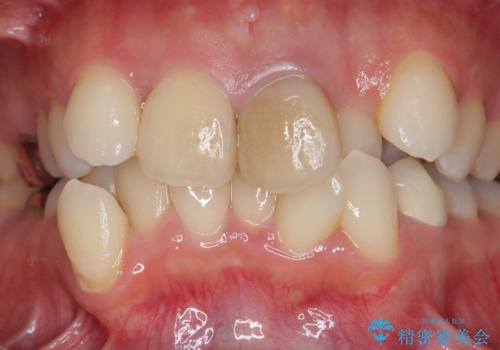

子供の頃にぶつけた前歯 根管治療から行うセラミック治療

歯根の近接のみられる右上側切歯を抜去し、根管治療を伴うセラミック治療を計画します。

- 26万円(仮歯・ファイバーコア・ジルコニアクラウン×2)費用は治療当時の料金となります